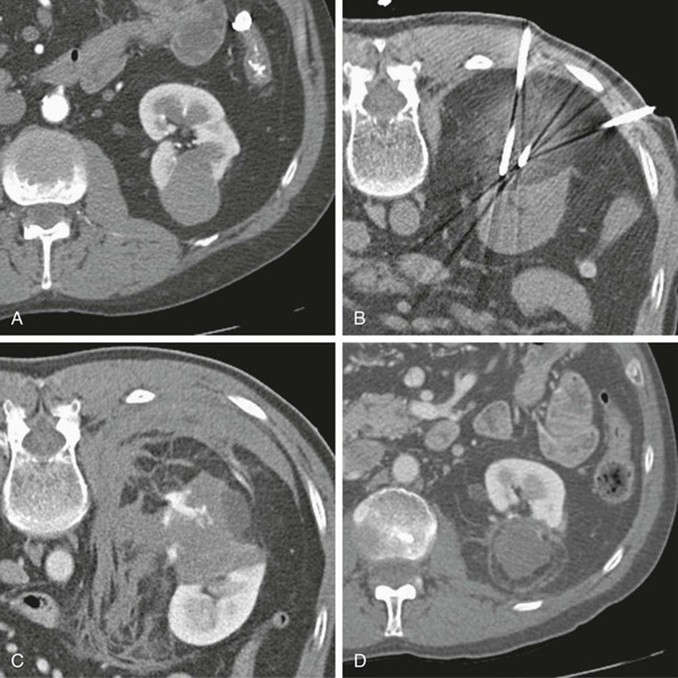

Cắt lớp vi tính

CT được sử dụng rộng rãi cả trong chẩn đoán và phân giai đoạn ung thư biểu mô tế bào thận. Trên CT không tiêm thuốc cản quang, tổn thương thường có tỷ trọng mô mềm, dao động trong khoảng 20–70 đơn vị Hounsfield. Các khối u lớn thường có những vùng hoại tử, và khoảng 30% trường hợp có vôi hóa. Trong thì vỏ–tủy, từ 25 đến 70 giây sau tiêm thuốc cản quang, ung thư biểu mô tế bào thận biểu hiện mức độ ngấm thuốc thay đổi, thường thấp hơn so với vỏ thận bình thường. Các tổn thương nhỏ có thể ngấm thuốc tương đương nhu mô vỏ thận và do đó khó phát hiện.

Nhìn chung, các khối u nhỏ thường ngấm thuốc đồng nhất, trong khi các khối u lớn hơn có hình ảnh ngấm thuốc không đều do sự hiện diện của các vùng hoại tử. Phân nhóm tế bào sáng có thể cho thấy mức độ ngấm thuốc mạnh hơn rõ rệt.

Thì vỏ–tủy cũng là thì tối ưu để đánh giá giải phẫu mạch máu, bao gồm xâm lấn tĩnh mạch thận và các biến thể động mạch, đặc biệt khi đang cân nhắc phẫu thuật cắt thận bán phần. Sự phát triển của khối u vào trong lòng hệ tĩnh mạch, đặc biệt là tĩnh mạch thận, xảy ra trong khoảng 10% trường hợp (dao động 4–15%). Tiên lượng ở những bệnh nhân có xâm lấn tĩnh mạch chủ dưới xấu hơn rõ rệt so với trường hợp chỉ xâm lấn tĩnh mạch thận, do đó việc nhận diện chính xác trên CT có ý nghĩa quan trọng.

Thì nhu mô thận, từ 80 đến 180 giây sau tiêm thuốc, là thì nhạy nhất để phát hiện các vùng ngấm thuốc bất thường.

Thì bài xuất ít giá trị hơn, nhưng vẫn quan trọng trong việc đánh giá giải phẫu hệ thống đài bể thận, đặc biệt ở những bệnh nhân có khả năng là ứng viên cho phẫu thuật cắt thận bán phần.

Chẩn đoán hình ảnh theo dõi sau điều trị thường được thực hiện bằng CT, trong đó khuyến cáo chụp hai thì ổ bụng nhằm tối đa hóa khả năng phát hiện di căn tạng đặc. Ung thư biểu mô tế bào thận thường gây di căn tăng sinh mạch, được thấy rõ nhất ở thì động mạch khi chụp vùng bụng trên.